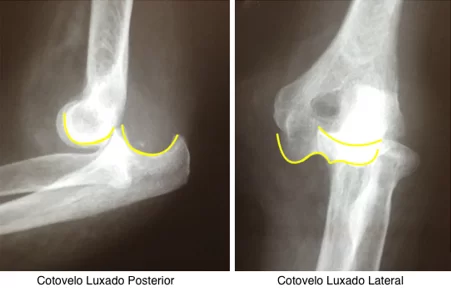

O exame de imagem inicial é uma radiografia do cotovelo de frente e perfil para avaliarmos a direção da luxação e a presença de fraturas associadas. A direção da luxação mais comum é posterior.